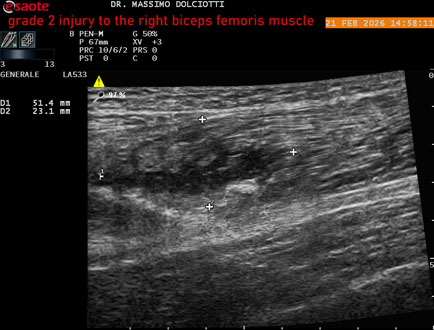

Ecografia del: 21/02/2026

Età Paziente: M 49 anni

Motivazione dell'esame: da 10 giorni dolore insorto durante la corsa.

Commento all'esame: le immagini ed il video documentano, al muscolo bicipite femorale destro, in sede prossimale, area disomogenea, ipoecogena, delle dimensioni di 27 x 24 mm (misura ottenuta per asse corto o trasversale) e delle dimensioni di 51 x 33 mm (misura ottenuta per asse lungo o longitudinale), da ricondurre a lesione muscolare di 2° grado con modica raccolta sieroematica intramuscolare.

Conclusioni: lesione di 2° grado al muscolo bicipite femorale destro (grade 2 injury to the right biceps femoris muscle).